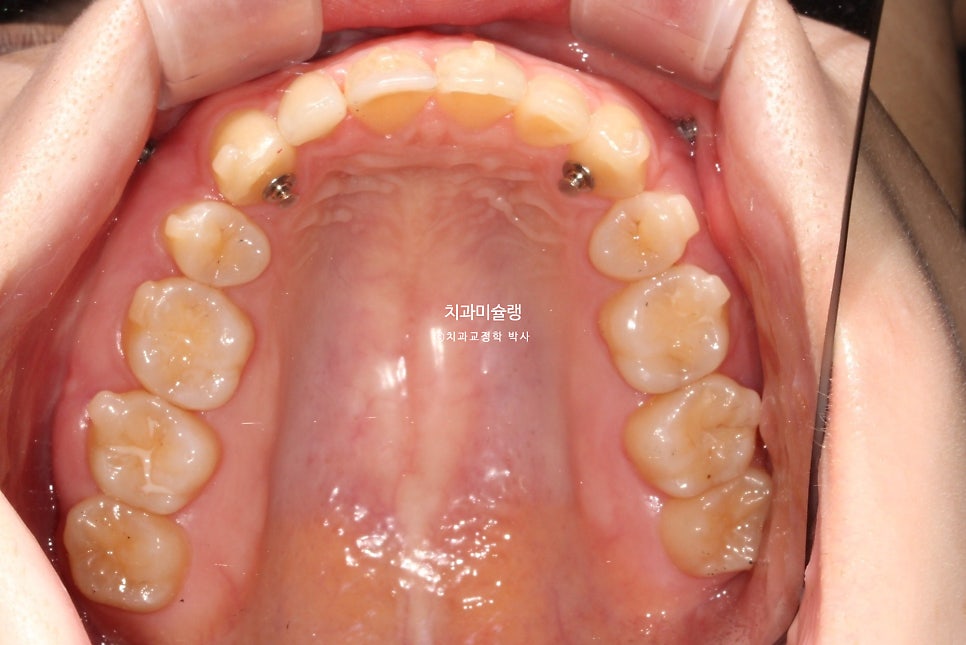

뽀족했던 악궁모양이 돌출된 앞니가 뒤로 들어가며 둥근 현태가 되었습니다.

작은어금니를 2개 뺐지만, 치아갯수는 14개로 정상입니다. 사랑니가 큰어금니 역할을 하고있기 때문이죠.

2023.04-2026.01